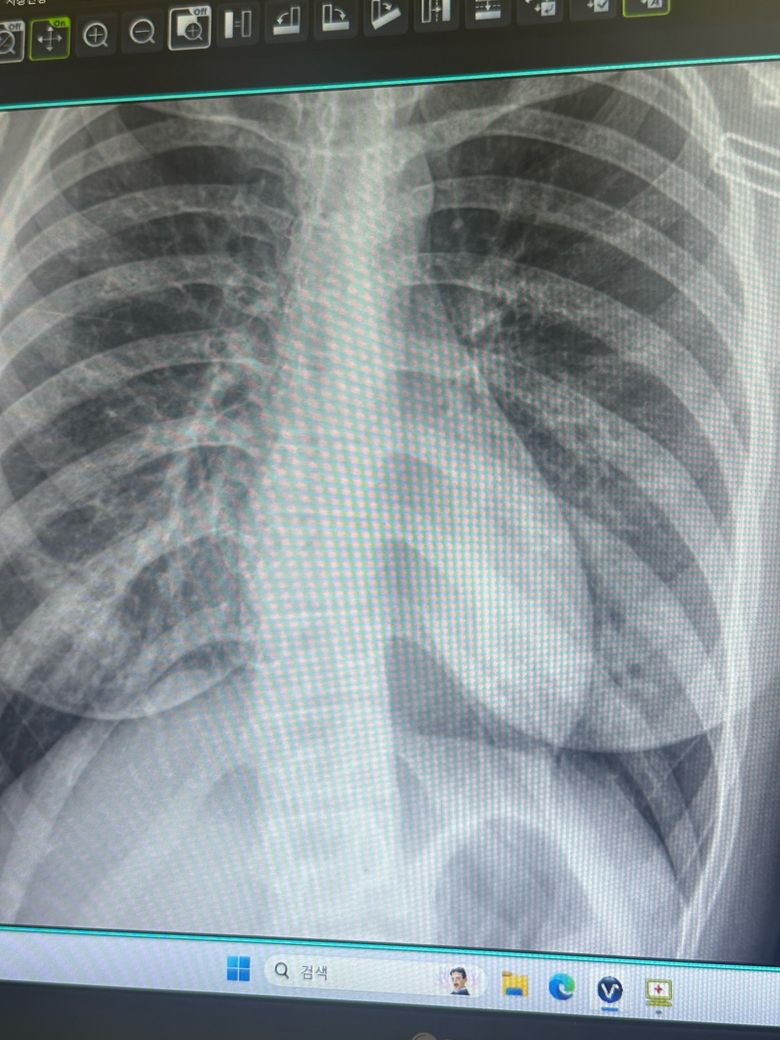

폐 엑스레이를 찍었는데 폐에 하얀색이 너무 많아요

사진을 보시면 전체적으로 하얗지는 않았는데 왼쪽 오른쪽 폐에 흰색이 많이 보여요 내일 CT를 찍을거지만 너무 걱정이 되어서 올려봅니다 ㅠㅠ 많이 심각할까요 기침이랑 가래가 2달 째라 폐렴인 것 같다는 생각이 들긴하는데 상태 보고 알려주세요

제가 판단하기에는 문제 없는 X-ray로 보이며 하얀색으로 보인다고 하시는 부위는 기관지의 정상 음영이지 문제있는 모습으로 보이지 않습니다.